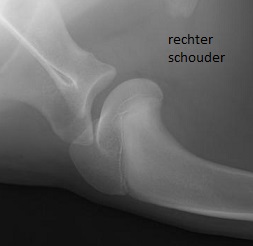

Ze kwamen op consult bij dokter Wilbert Winkelmolen en tijdens het onderzoek bleek dat Buddy drukpijnlijk was op al zijn pijnbeenderen. Dat duidt inderdaad op groeipijn. Daarnaast reageerde Buddy ook pijnlijk bij het bewegen van zijn linker schouder. Er werd besloten om meteen röntgenfoto's te maken van al zijn gewrichtend onder narcose.

Zijn rechter schouder was keurig, maar ter hoogte van zijn linker schouder was er een afwijkende rand aan de onderkant van het schouderblad zichtbaar. Dit duidt op osteochondrose: een erfelijke kraakbeenziekte, die voorkomt bij honden tussen de 4 en 10 maanden leeftijd. Hierbij wordt het kraakbeen te dik, waardoor stukjes kraakbeen kunnen afsterven en los kunnen raken in het gewricht. Dit kan de nodige pijn en irritatie in een gewricht veroorzaken, waardoor een dier continue mank gaat lopen.

Het rechter schoudergewricht is keurig, links lijkt er wel een klein hapje uit de onderkant van het schouderblad te zijn genomen, bij de groene pijl. Dat is osteochondrose, met de verdenking op een los stukje bot in het gewricht.